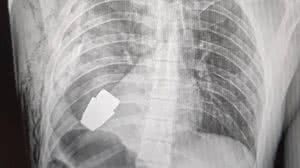

Soldado ucraniano tem granada não detonada removida do tórax em cirurgia